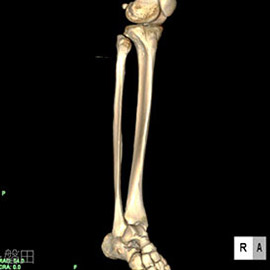

80列マルチスライスCT 検査 画像例

80列マルチスライスCTで撮影した画像

整形